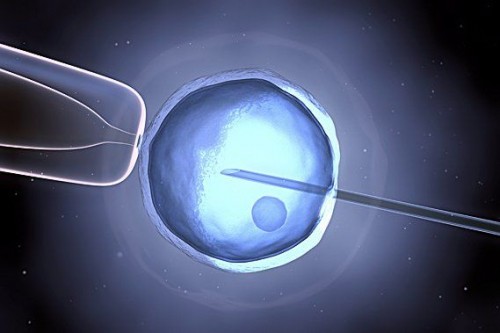

Fecondazione eterologa: costi, strutture ed esami per accedervi